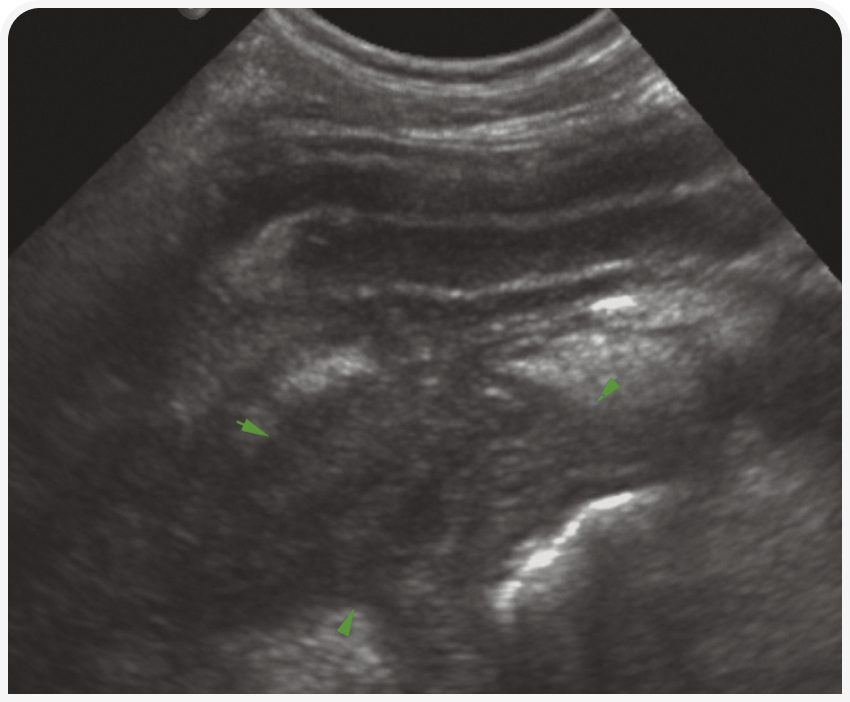

При остром панкреатите поджелудочная железа обычно гипоэхогенна, неоднородно утолщена и окружена гиперэхогенным и разреженным слоем жировой ткани. Также вблизи поджелудочной железы часто скапливается жидкость. Прилежащая стенка двенадцатиперстной кишки часто утолщенная и складчатая, ее слои нечеткие (Рисунок 7). Обследование поджелудочной железы часто затруднено из-за боли в животе, поэтому требуется обезболивание или седация. Могут образоваться сопутствующие абсцесс или киста, проявляющиеся округлой структурой, заполненной жидкостью от гипоэхогенной до анэхогенной плотности. Такие поражения можно дренировать под контролем УЗИ. Хронический панкреатит распознать сложнее; он характеризуется появлением в паренхиме поджелудочной железы гетерогенных участков и прилегающих к ней очагов гиперэхогенной жировой ткани.